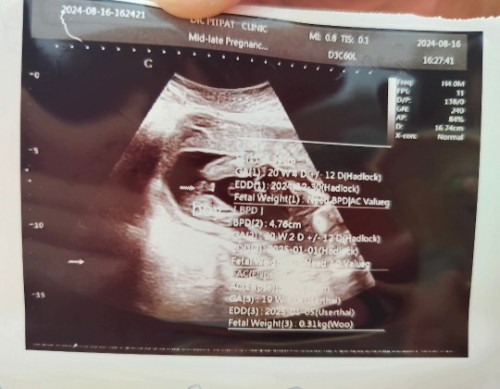

ไปซาวด์มาสดๆร้อนๆเลยค่ะ บ้านนี้หมอบอกไม่มีลุ้นเลยโผล่ชัดเจน ได้ผช .สมใจคุณพ่อ👶

ถ้าผู้ชายจะเห็นเป็นก้อนๆบวมๆอ่ะค่ะ บ้านนี้น้องผช.

อันนี้ลูกชายค่ะ เห็นตอน 13วีค โผล่มาเป็นแท่งเลย

ญ จ้า จิ๊มิ๊ชัดมากก ถ้า ช จะมาเป็นแท่งเลยแม่

เชื่อหมอเถอะค่าบ้านนี้จู๋โผล่มาเลยตอน20วีค

100%ผู้หญิงค่ะ ภาพเหมือนของเราเลย ชัดเจน